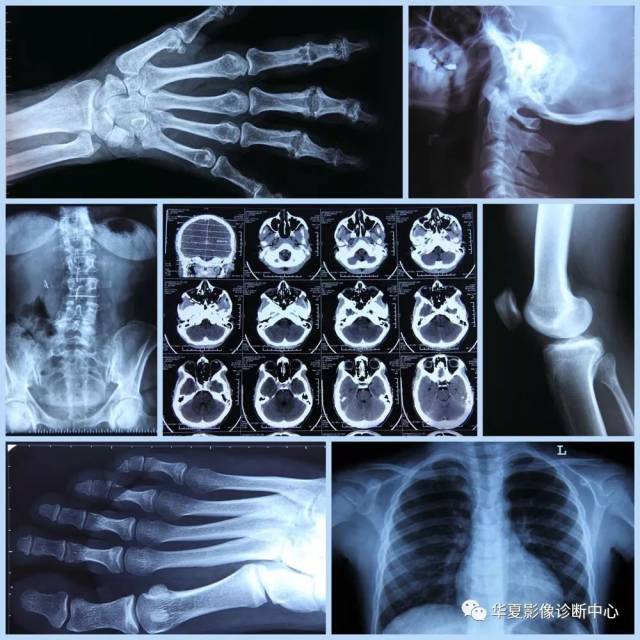

胸腔x光片棚拍

图片尺寸800x1200